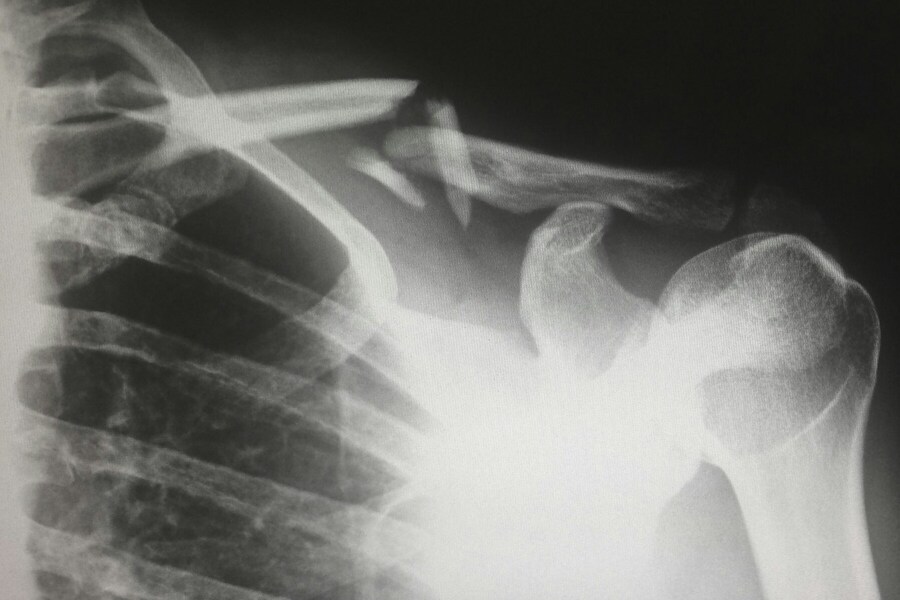

Lastly, there are more serious but less common risks that travelers should be aware of, such as sprains, strains, or allergic reactions. A twisted ankle on a rocky path or an unexpected severe allergy can escalate quickly. Having the right supplies and knowing how to use them can provide crucial first-line treatment while you seek professional medical help. Being prepared for these eventualities isn't about being paranoid; it's about being practical and ensuring you have the tools to handle a wide range of scenarios that can arise when you're away from home.